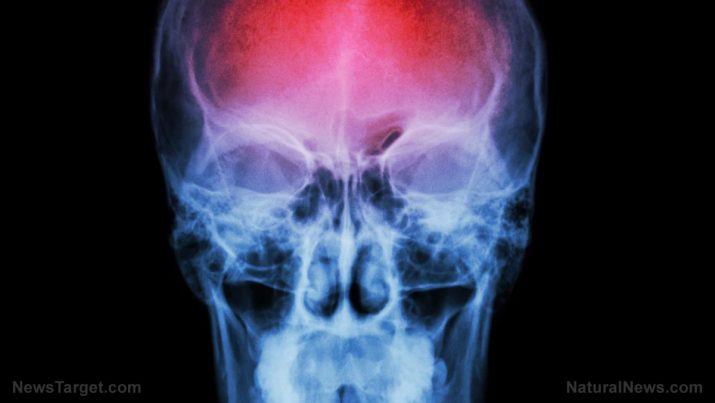

A guide to identifying and treating strokes, both on and off grid

A stroke can happen anytime and anywhere. This includes locations far away from professional healthcare, modern medicine, and well-equipped treatment facilities. An article in Doom And Bloom covered how you can identify a stroke and treat victims of these attacks whether you are on the grid or off it.

Most strokes are ischemic in nature. Ischemic strokes are caused by a blood clot blocking up an important vessel that supplies blood to the brain.

However, if the victim is known to have hypertension, avoid administering blood thinners. Elevated levels of blood pressure can cause a different type of stroke called a hemorrhagic stroke, where blood that gets into brain tissue essentially squeezes brain cells.

Some hemorrhagic strokes might also be caused by aneurysms, a balloon-like flaw in the wall of a blood vessel. The pressure exerted by flowing blood can cause this flaw to burst open, allowing blood to leak into the brain and cause stroke.